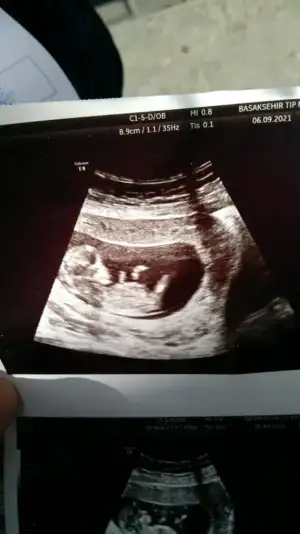

• 67C7BD9F-AC6D-4A5A-9B03-A91019DC907A.webp

67C7BD9F-AC6D-4A5A-9B03-A91019DC907A.webp

36,9 KB · Görüntüleme: 100

Kızlar benimkinede bakar mısnz? Karın ultrasonu 12+2 de yiz.

Bi fikri olan varmı kızlar ben anlamadım nubtan